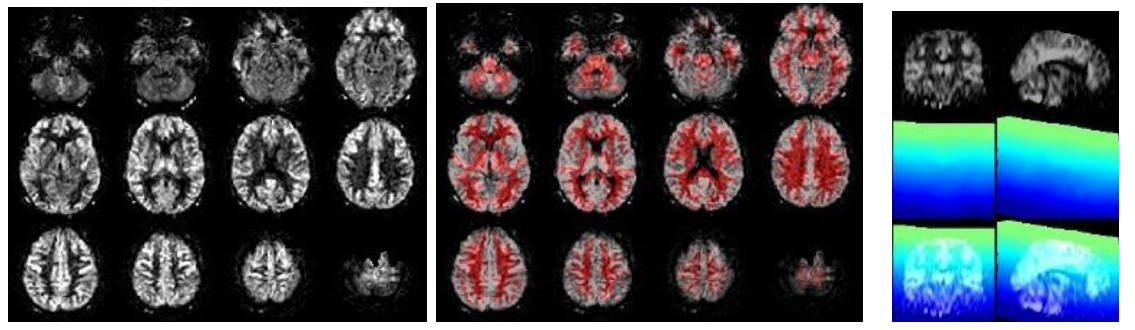

The ASL module processes the perfusion (ASL, M0) images, from motion correction to registration to quantification and PV correction. Check for general ASL quality, vascular artifacts, good GM-WM contrast, WM-CSF contrast, artifacts on the temporal standard deviation (SD) images, geometrical distortion, and signal drop out from EPI susceptibility artifacts, whole-brain coverage (slice_gradient). Check also for registration to standard space, all images should be in the same position/orientation, i.e. meaning that you always see the same slices, with the same angulation. Check for motion artifacts as a bright halo around the CBF and temporal SD images. In a study QC report, you could show some worst, median, and best examples. Check (from left to right):

//Population/ASLCheck/Tra_qCBF_untreated_*ASL_*.jpgfor the CBF images without vascular treatment (qCBF*)//Population/ASLCheck/Tra_Reg_pWM_qCBF_untreated_*ASL_*.jpgfor the ASL->T1w registration (T1w WM segmentation in red)//Population/SliceGradientCheck/SliceGradient_*.jpgfor the orientation of native slices in MNI space

If time-series exist (from left to right):

//Population/RawSourceIMCheck/Tra_mean_control_*.jpgfor the inspection of the average ASL source image//Population/SD_SNR/Tra_SD*ASL_*.jpgfor the temporal SD image. This should be a smooth, noisy image, with only vascular peaks.//Population/MotionASL/rp_*ASL*motion.jpgto inspect subject motion (net displacement vector)//Population/MotionASL/rp_*ASL*threshold_free_spike_detection.jpgto inspect the performance of ENABLE